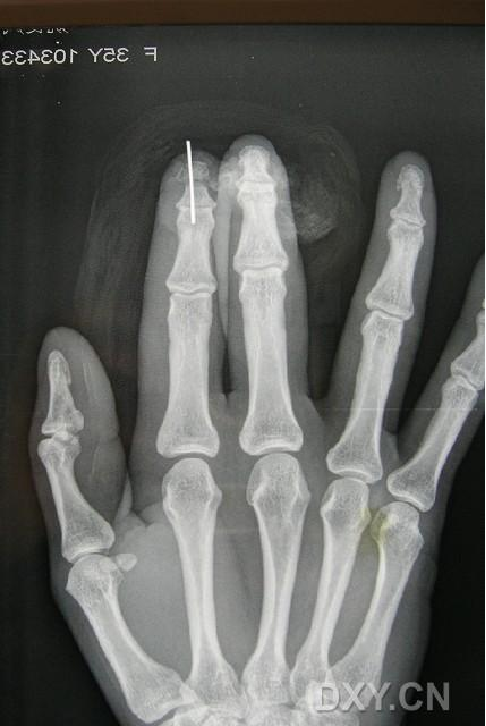

指动脉逆行岛状瓣  CASE

CASE